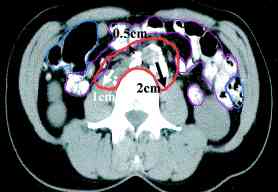

cervix ports, the node positions on CT scans (IJROBP

2002;54:1147) (A) Furthest

distance from lymph node to vessel wall. (B)

Para-aortic lymph node CTV. (C)

Common iliac lymph node CTV. (D)

External iliac CTV, including lateral group. (E) External

iliac CTV, including medial (obturator) group. (F)

Inguinal lymph node CTV. CTV depicted by thick orange line.

Small bowel demarcated by thin magenta, large bowel by thin

blue, rectum by thin dark purple, bladder by thin turquoise, and

uterus by thin yellow-green line. RTOG atlas